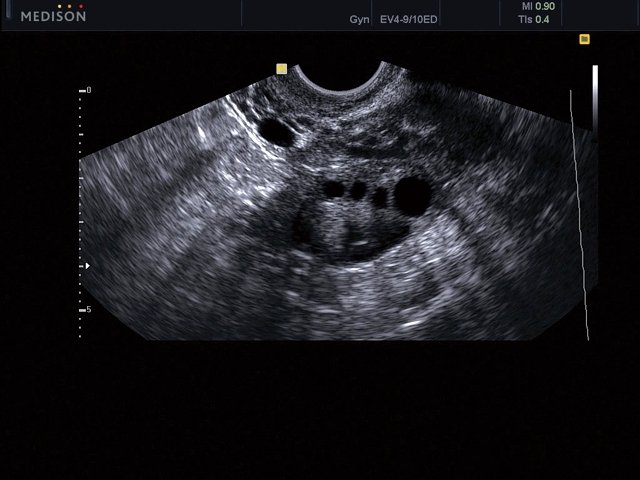

Яичник, B-режим (эхограмма №467)

[EN] Эхограмма №467: Яичник в B-режиме (полостной датчик 4-9 МГц).

Изображение получено с помощью УЗ аппарата MySono-U5 (снят с производства).